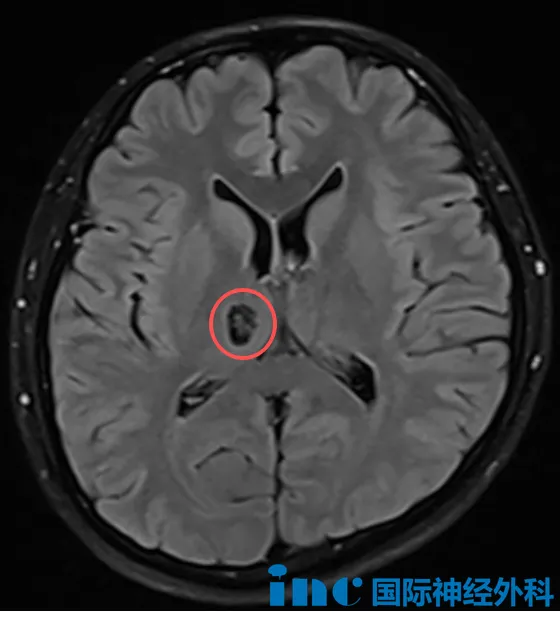

最新磁共振检查显示:脑干部位存在一个约16×11×14mm的"爆米花"状异常信号病灶。这个位于生命中枢的病变正在影响孩子的健康状况和未来发展。目前达恩主要表现为右侧肢体无力和轻度面瘫,其他神经功能尚属正常。

一次常规体检中,28岁的孙先生意外发现右侧丘脑存在14mm×10mm占位病变。虽然目前没有任何神经功能症状,但这个颅内"不速之客"让他陷入两难:无症状的脑部占位该如何处理?手术的最佳时机是什么时候?